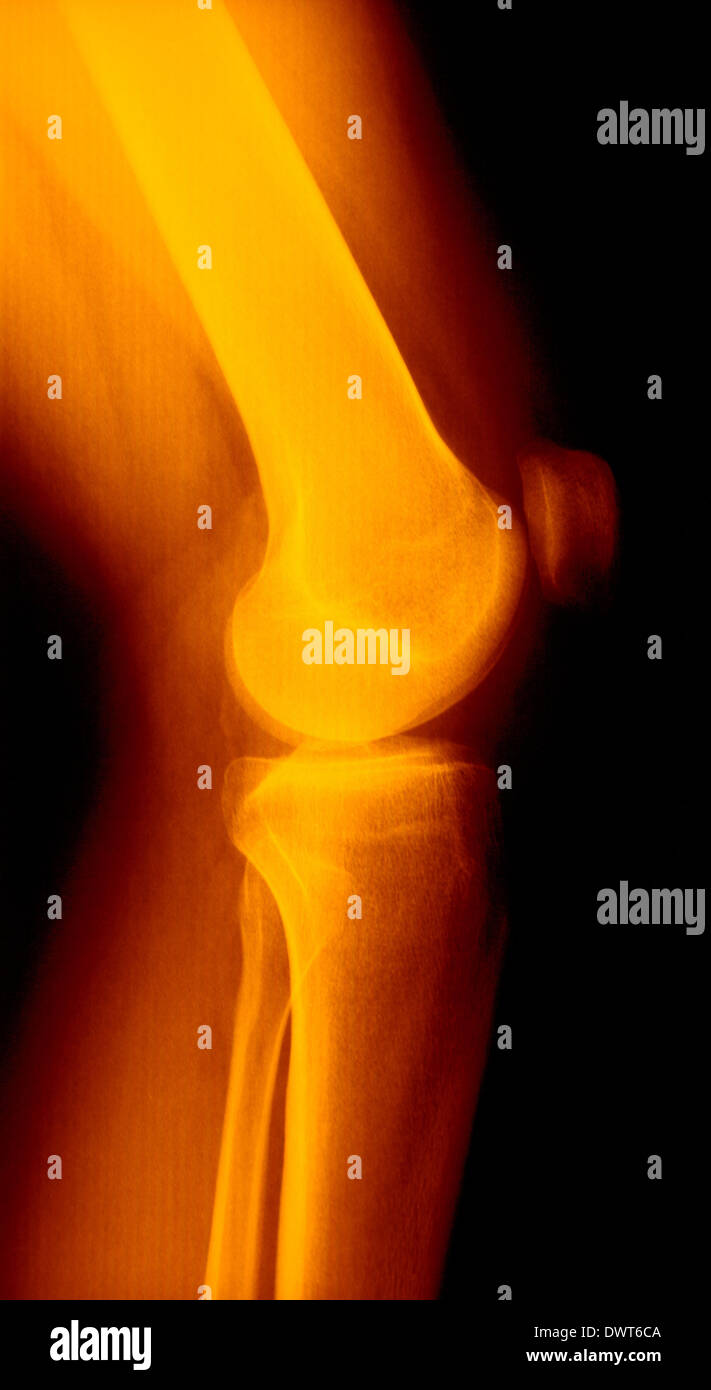

From www.alamy.com

Knee x ray Stock Photo Alamy What Can A Knee X Ray Diagnose This can help them diagnose osteoarthritis. a recommended systematic checklist for reviewing musculoskeletal exams is: while magnetic resonance imaging (mri) is widely. Soft tissue areas, cortical margins, trabecular. Knee joint space narrowing is a clinical sign of arthritis of the knee. What Can A Knee X Ray Diagnose.